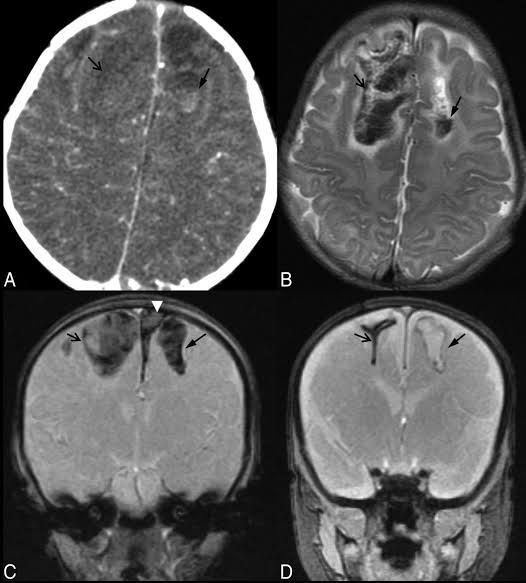

Cerebral lacerations are tears in brain tissue, caused by a foreign object or pushed-in bone fragment from a skull fracture. Motor vehicle crashes and blows to the head are common causes of bruises and tears of brain tissue. Symptoms of mild or severe head injury develop.